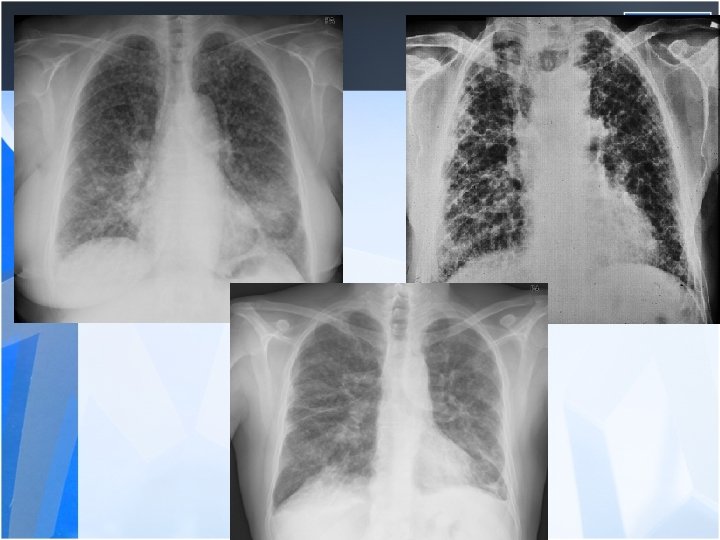

• Radiology is the most important diagnostic method for silicosis • Mainly upper and middle zone 3 -10 mm noduler opacities (silicotic nodules) • ILO clasification p, q, r • Hiler calcification (Egg shell calcification) PMF: • Coalescence of radiologic opacities (conglomeration • Nodules>10 mm • ILO clasification A, B, C • Honey combing can be seen in end stage disease

Coal Workers Pneumoconiosis • The respiratory condition that results from the inhalation and deposition of coal dust and tissue reaction (in miners or exposure outside) • Simple CWP – 5 -10 years old coal dust exposure – Small rounded opacities, first in the upper zones but as the disease advances mid and lower zones can become involved – Small emphsemateus changes around the nodule (coal macule) – Usually normal lung function unless associated with smoking – Asymptomatic in the early stages • PMF – Severe progressive shortened ventilatory capacity and life span (reason? ) – Progressive dyspnea – Large opacities sometimes may necrose and cavitate – Mixed type respiratory function decrease – Black sputum: melanoptisis – Poor prognosis